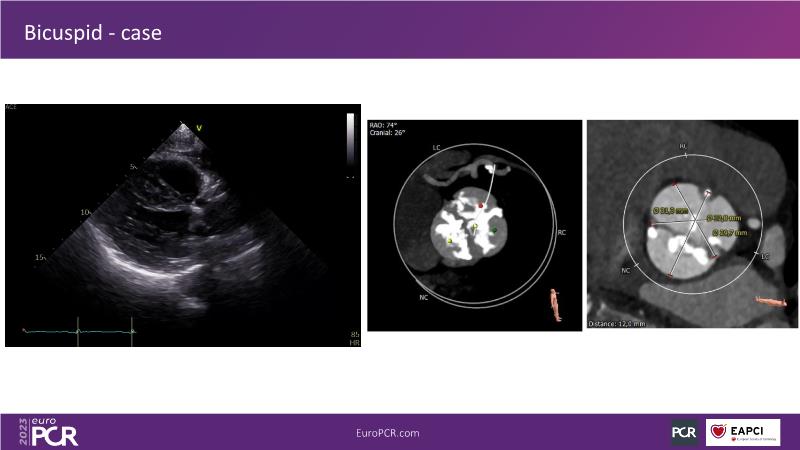

Discover the key factors to consider in selecting the optimal valve and implant technique for transcatheter aortic valve implantation (TAVI) to achieve optimal procedural outcomes. Gain insights into the impact of device choice and implantation technique on coronary access following TAVI and learn valuable strategies for tailoring your TAVI technique to complex scenarios, including bicuspid aortic valves, large and calcified anatomies, and ensuring coronary access.

- To learn how to tailor your TAVI technique to complex situations: bicuspid aortic valves, large, calcified anatomies and coronary access